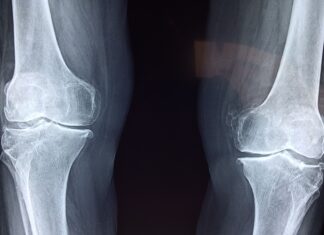

Artrosi del ginocchio: la fisioterapia digitale migliora dolore e funzione

Le tecnologie digitali stanno assumendo un ruolo crescente nella riabilitazione dei pazienti con patologie muscoloscheletriche. Una nuova revisione...